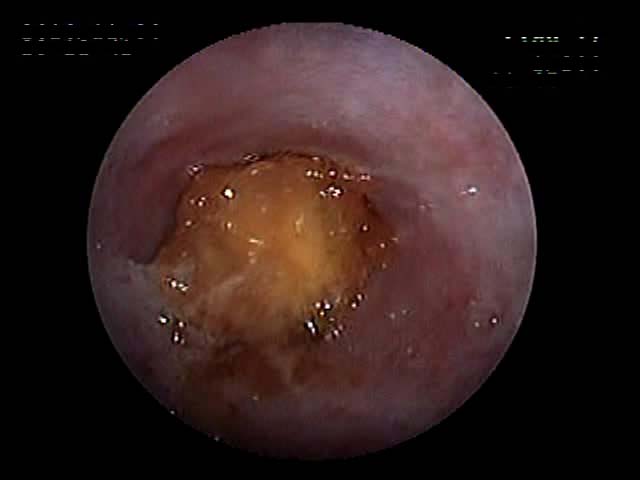

先日、といっても年末になります。リンゴの芯を与えてから吐き続ける5kgのワンちゃんでした。夜中になっても止まらないとのことで、内視鏡で確認したところ、食道と胃の間で引っかかっていました。内視鏡に工夫をして、胃の中に押し込むことに成功しました。

写真は、押し込んでいる時と、押し込んで胃の入り口が閉まる瞬間です(入り口が炎症を起こして赤くなっています)。